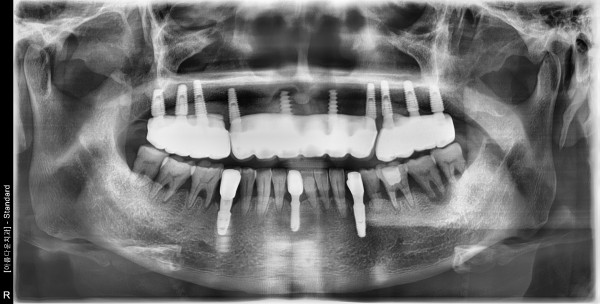

60대 남성 임플란트 식립